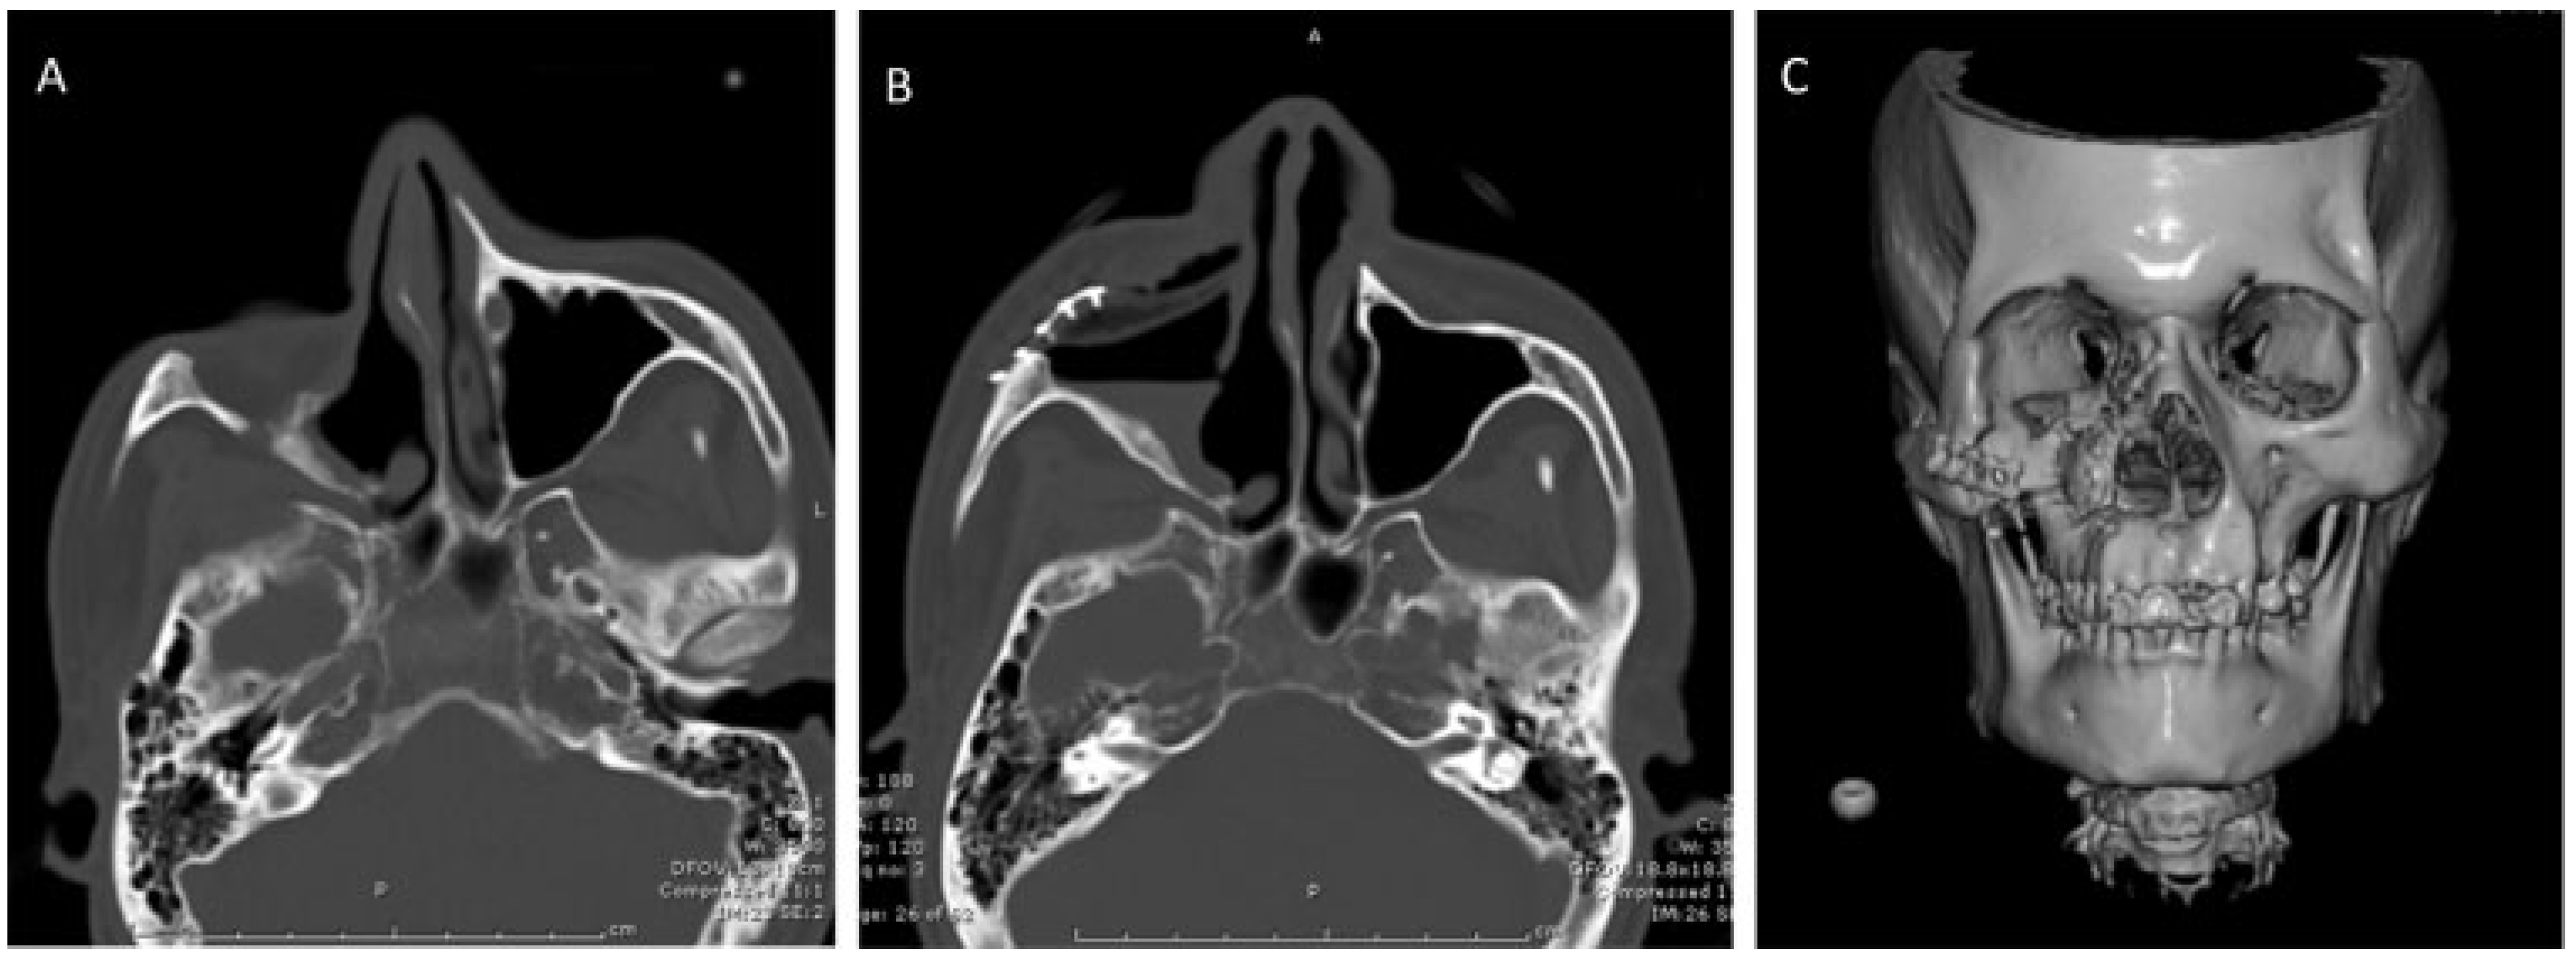

During the initial consultation, craniomaxillofacial computed tomography (CT) scan was ordered with 1 mm cuts for preoperative planning and to assess the extent of the right zygomaticomaxillary defect (Figure 2A). A 3-D model was made from the CT scan images (Figure 3) for preoperative shaping of the right 2/3 orbital porous polypropylene implant, which would be used to help with the intraoperative shaping of the implant.

The 3-D model was then placed in a sterile X-ray cassette cover and brought onto the surgical field where the porous polypropylene implant was modified to fit into the defect with Mayo scissors and a cutting burr (Figure 5). Care was taken to ensure symmetric orbital floor height and malar projection with the contralateral structures on the 3-D model. Once the implant appeared to fit well into the model it was placed into the patients defect. Minor modifications to the implant were made to address any additional soft tissue that the 3-D model did not take into account. The implant was then secured to the craniofacial skeleton with standard gold midface plates and 1.2 mm screws (Stryker Leibinger Midface module, Stryker Craniomaxillofacial (CMF), Portage, MI) (Figure 6). The wound was then irrigated. The medial canthal tendon was then reattached to the tendon remnant on the facial skeleton with a 5–0 nylon suture. The skin flap was anchored to the infraorbital rim portion of the implant with three 4–0 polydioxanone sutures (Ethicon, Cornelia, GA) in simple interrupted fashion. The remaining facial incision was closed in layers (Figure 7). An immediate postoperative CT scan showed adequate anatomical reconstruction of the zygomaticomaxillary defect (Figure 2B,C).

Figure 2. (A) Preoperative craniomaxillofacial computed tomography (CT) scan revealing zygomaticomaxillary defect. (B) and (C) Postoperative CT scans with three-dimensional reconstruction showing visualization of the fixation hardware attaching the implant to the remnant of the zygoma recreating the anterior wall of the maxillary sinus.